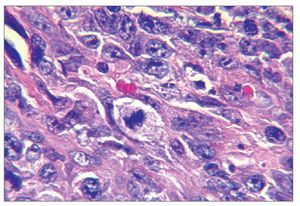

El examen histológico mostró un fuerte infiltrado difuso constituido por células blásticas linfoides grandes que presentaban núcleos ovoides y nucleolos prominentes, con presencia de numerosas mitosis atípicas (figs. 2a y 2b). La inmunohistoquímica mostró células pleomórficas positivas para CD20 y negativas para CD30, CD3, y anticuerpos Alk, confirmando el diagnóstico de LNH difuso de células B grandes (figs. 2c a 2f). Una vez completado el estudio se descartó linfoma sistémico.

Figura 2b. Campo que muestra mitosis atípicas (hematoxilina-eosina; 40 aumentos originales).